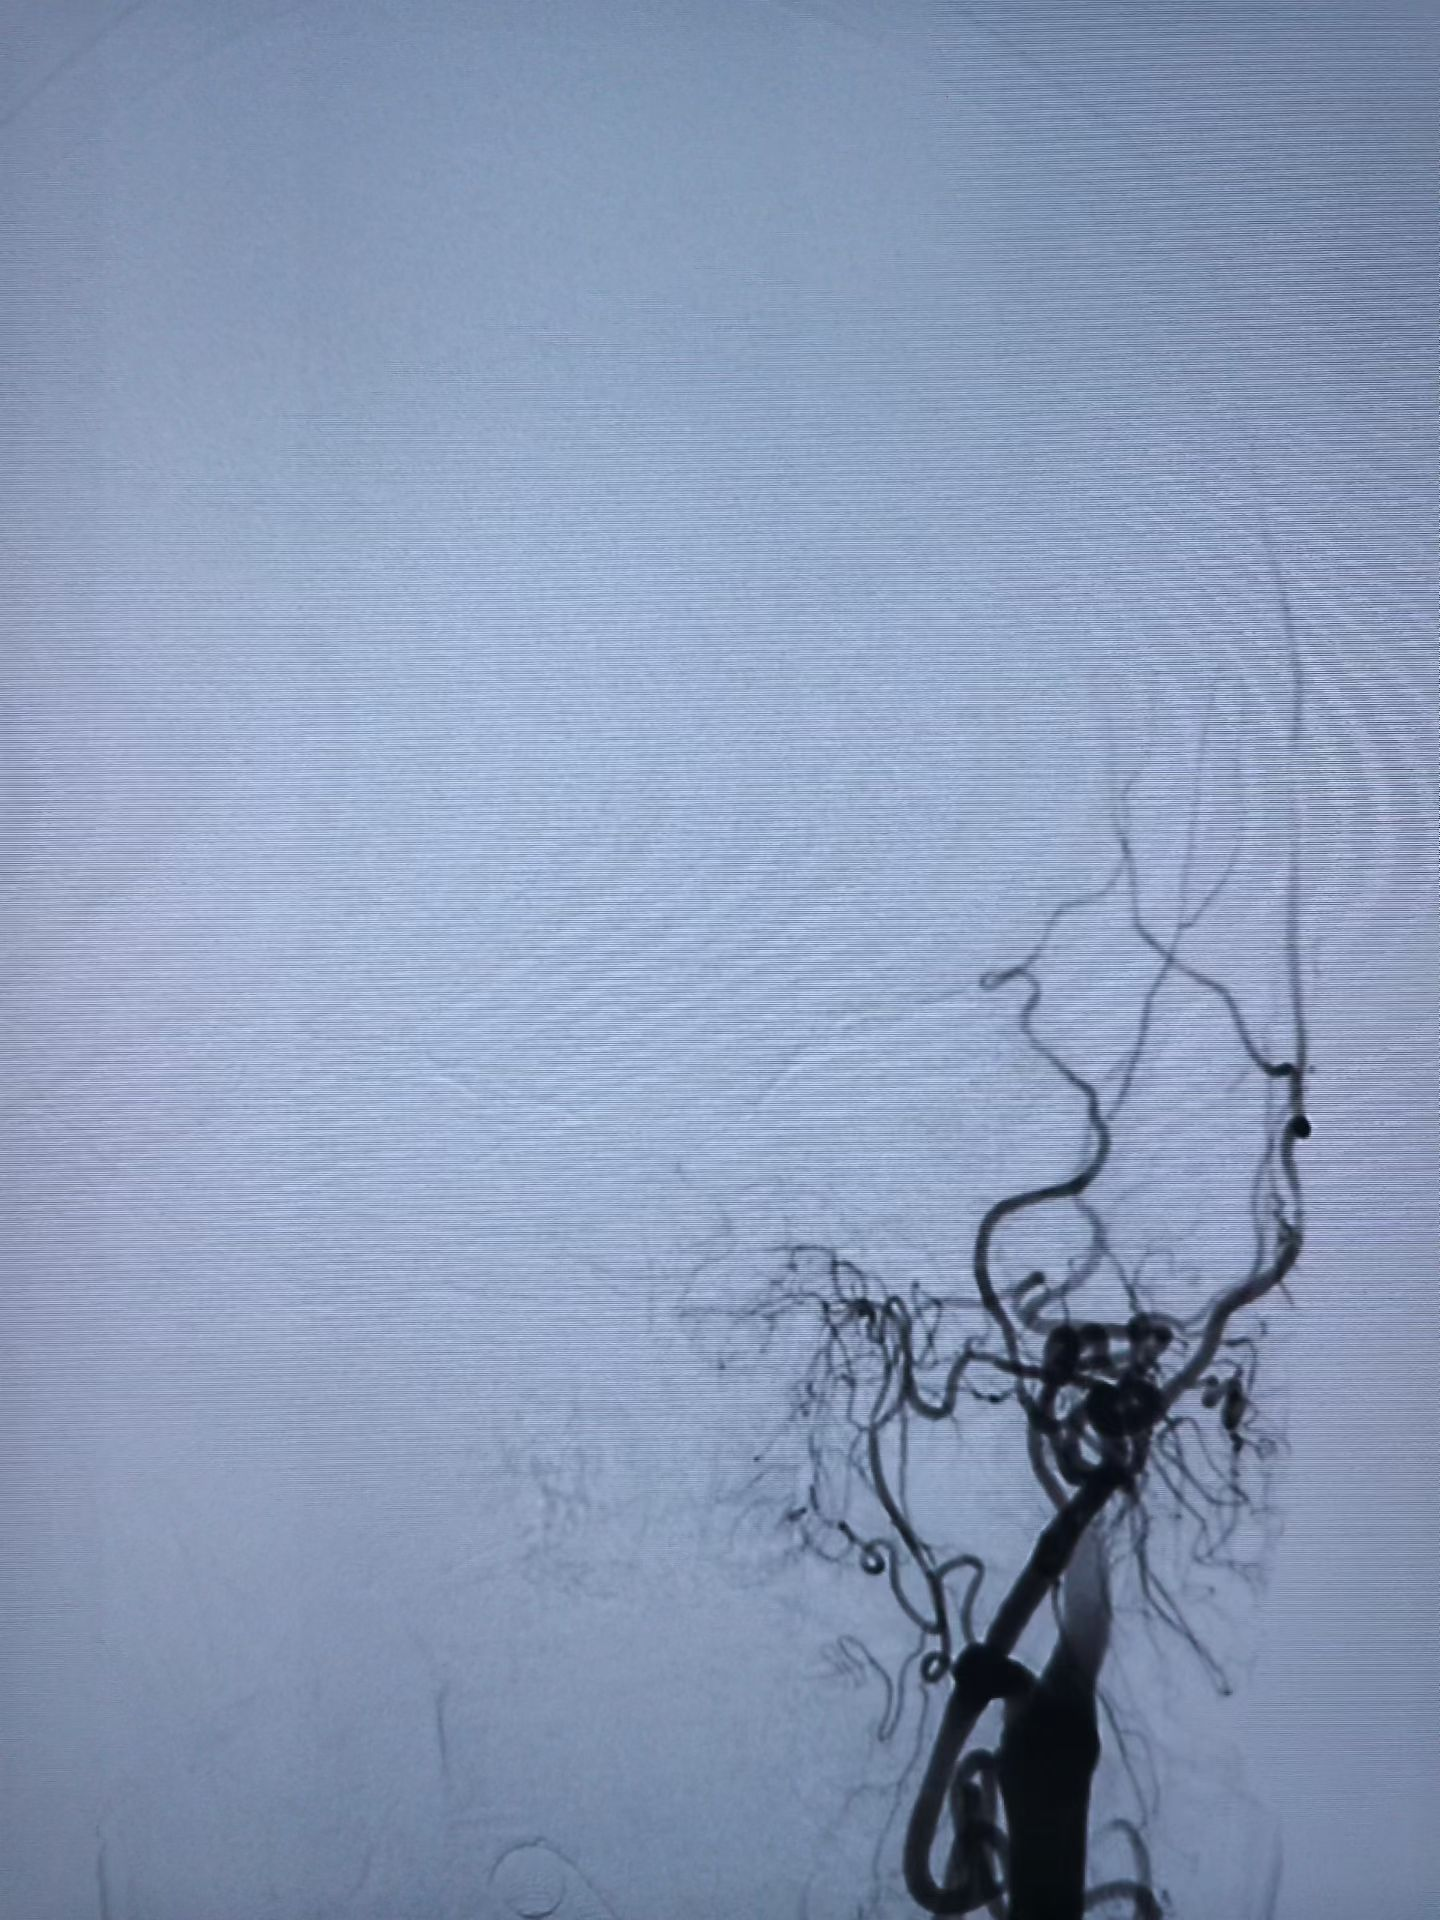

与家属充分沟通后,医疗团队决定迎难而上,为王奶奶实施了“取栓支架保护下脑动脉取栓术”,在一个小时内成功将堵塞在左侧颈内动脉及大脑中动脉的大量血栓取出,瞬间恢复了大脑供血。

急诊介入手术前后血管